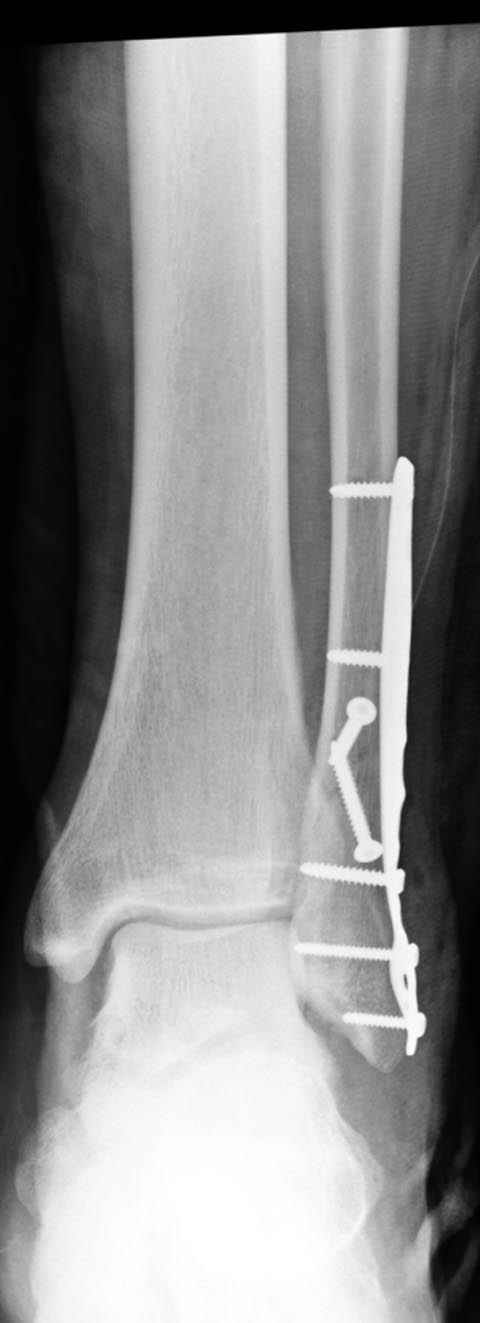

Тему неоднократно разбирали (см. архив), как всегда, недостаточны ренгенологические исследования - кроме прямого и боковых снимков, еще нужна косая ренгенограмма для определения ankle mortise, без мортиз снимка трудно определить высоту и ротацию малоберцовой. (снимки)

Показания для фиксации: укорочения и ротация малоберцовой, особенно обращают внимание на любой подвывих таранной кости: неустраненый подвывих впоследствии приводит к раннему артрозу. Задний край фиксирует тогда, когда перелом составляет около 25% суставной поверхности голеностопного сочленения и смещение более 2мм.

По снимку ваш случай относится к Weber В, фиксацию производят восстановлением длины малоберцовой кости, под ренгеном (ЭП)контролем, для этого я предпочел бы латеральный доступ, остеотомия по линии перелома, удлинение малоберцовой засчет скоса линии остеотомии, компрессия “lag technique”по линии остеотомии и фиксацию провести латеральной пластиной. Отдельный задний доступ, остеотомия по линии перелома, репозиция и фиксация заднего края вашим предпочтительным методом: 3.5мм шурупом с шайбой или пластиной Antiglide Butress

method. При восстановленном суставе, уменьшится медиальная щель, а при Weber В повреждается только передне-нижняя межберцовая связка синдесмоза, повреждение которой приводит к наружной ротации

малоберцовой, но после восстановления всех смещений, связка автоматический приближается к исходному и нет необходимости восстановления синдесмоза.